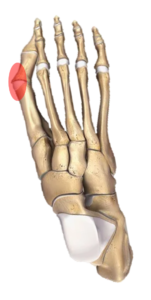

El hallux valgus o juanete, es la desviación del dedo gordo del pie hacia la parte externa. Es la deformidad más frecuente del pie que motiva consultas en traumatología.

Existen varios síntomas relacionados con la aparición del juanete. Lo más habitual es que se inicie la deformidad del dedo gordo, desplazándose la parte más distal (falange) hacia afuera. Esto provoca que el pie pierda su forma estética. Conforme el dedo se desvía, su parte más interna comienza a doler al rozar con el zapato y se genera un sobrecrecimiento óseo en la parte más interna de la cabeza del metatarsiano que conocemos como bunion.